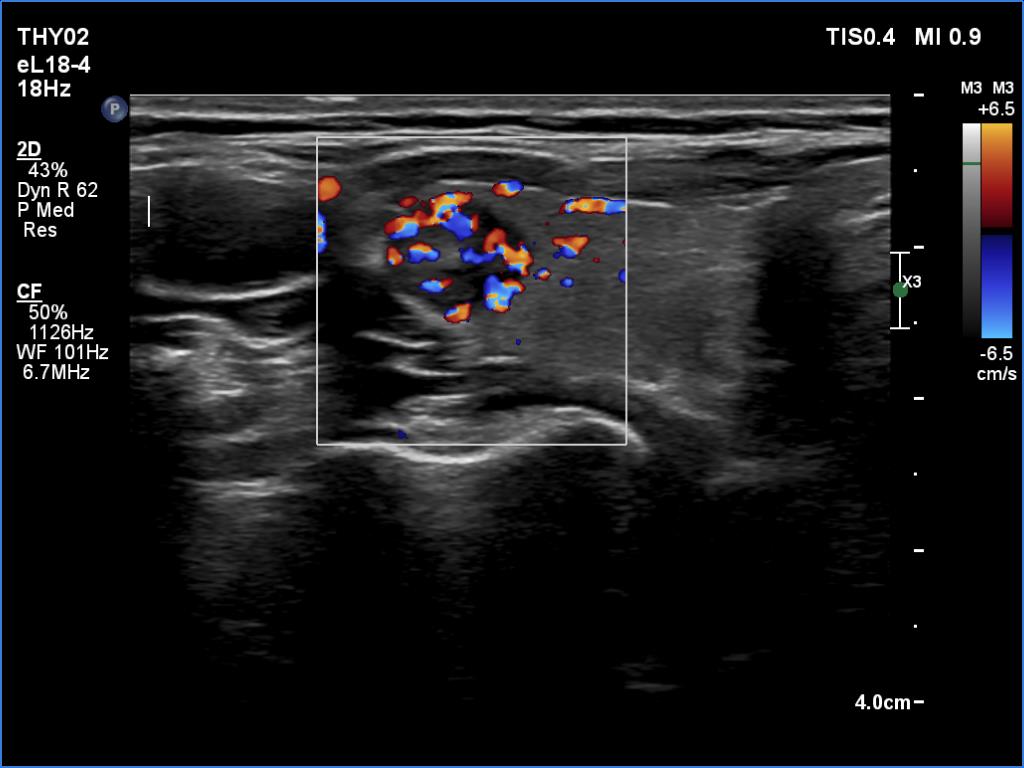

First examianation (first row of images):

Clinical data: A 43-year-old woman was referred for an evaluation of a thyroid nodule detected on screening.

Palpation: a not firm nodule in the right lobe.

Laboratory examination: TSH 2.05 mIU/L.

Ultrasonography. The thyroid was echonormal. There was a nodule in the ventrolateral part of the right lobe. The lesion was composed partly of hypoechogenic, partly of echonormal areas. There was one echogenic punctate focus within. The microflow imaging revealed increased intranodular blood flow. The ventral part of the lesion was hard on elastography.

Cytological diagnosis: papillary carcinoma.

A right lobectomy was performed. Histology revealed a T1a papillary carcinoma.